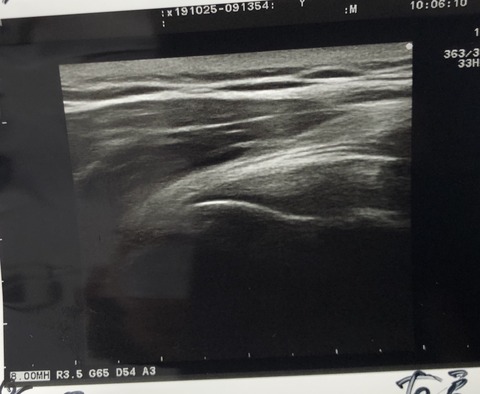

本日は、手指 中心の勉強会しました

保存的治療には、最高に役立ちます!

悩ましいCM関節症は、筋トレ、EMS、テーピング

ストレッチで、バッチリ 効果あり